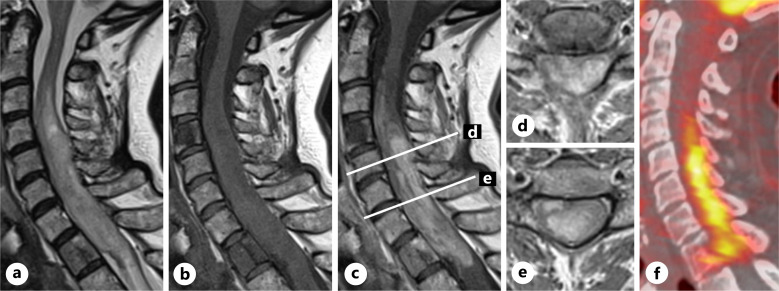

Case presentation: A 53-year-old female with a history of mediastinal Hodgkin lymphoma treated with chemotherapy and radiotherapy who subsequently developed thyroid cancer and breast cancer throughout her life was admitted due to slowly progressing spastic tetraparesis. Cervical MRI revealed an intramedullary lesion at the C4-T1 level, enlarging the spinal cord, with a heterogenous contrast enhancement and a lesion within T1 vertebral body showing contrast enhancement. Whole-body 18F-FDG-PET/CT revealed increased radionuclide uptake within the cervical spinal cord at the C2-C7 level and a focus of increased metabolic activity within the T1 vertebral body. The patient underwent a C4-T2 laminectomy with tumor debulking, and a biopsy of the T1 vertebral body was taken. Closure was performed with thecal sac expansion using a fascia lata graft and open-door laminoplasty. The histomolecular results confirmed the diagnosis of glioblastoma, IDH-wildtype (CNS WHO G4), in the cervical spinal cord lesion and breast cancer metastasis in the T1 vertebral body. Postoperatively, the patient experienced progression of lower extremities and left arm paresis. No adjuvant therapy was administered due to neurological deficit progression. The patient died 6 months after surgery.